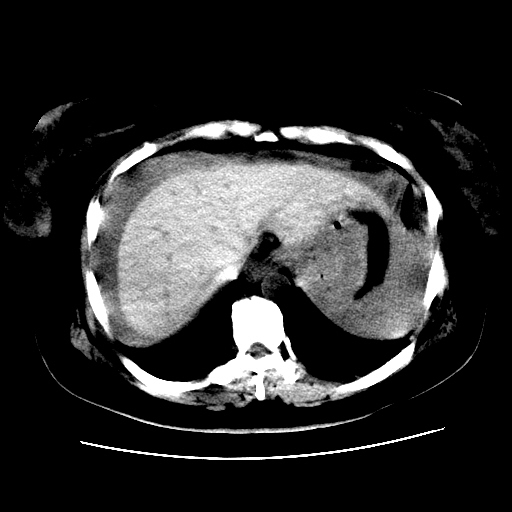

f,45y.怀孕4月晕倒,b超提示死胎,有手术结果,请展开讨论后明天告诉。

膈下-肠间隙内见气体密度影,子宫轮廓显示不清,宫腔-腹腔积液,首选考虑---子宫破裂出血。

1)宫腔妊娠。2)子宫破裂出血,腹腔及盆腔积血。

肝小可能是肝硬化,也可能是正常或畸形

腹腔积液,怎么来的可能是肝来的,也可能是别的来的

感谢同行们的高见。手术结果:子宫破裂出血。

我们的诊断是:腹、盆腔积液(考虑腹盆腔脏器破裂出血);宫腔妊娠。让人纳闷的是当时我们没有经验,现在回头看看分析:4月宫腔妊娠:1、洋膜囊不可能紧贴胎体这么小;2仔细看看子宫后壁肌层模糊不清;3腹、盆腔液体来源原因?4、45岁高龄妊娠有晕倒。由此可大胆诊断:宫腔妊娠子宫破裂出血。